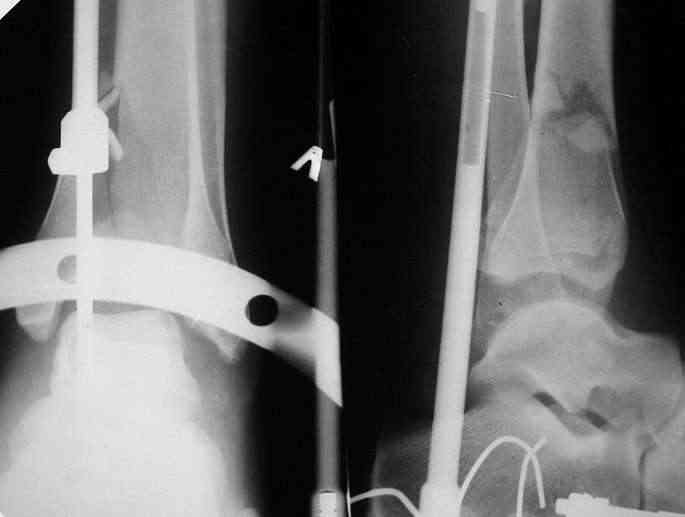

Здравствуйте, коллеги.Больной 26 лет, в 2004 году попал ко мне с диагнозом:синтезированный в аппарате Илизарова неполный внутрисуставной оскольчатый перелом дистального метафиза левой большеберцовой кости со смещением; выраженный остеопороз; множественное спицевое нагноение. Несостоятельность фиксации (костные отломки буквально "елозили" по спицам, несмотря наналичие упорных площадок).

Мной был демонтирован АВФ, удалены все спицы. Больной некоторое время лечился консервативно (шина Белера, антибиотики, перевязки). По заживлению и купировании гнойно-воспалительного процесса была произведена осткрытая репозиция, накостный остеосинтез 1/3 трубчатой пластиной.Такой вариант был принят из-за жуткого остеопороза и отказом больного от предложенного артродезирования голеностопного сустава сразу. Послеоперационный период без особенностей. Через год, больной пришел на осмотр на своих двоих, без дополнительной опоры, с жалобами на боли приходьбе в обл. г/стопа и с желанием замкнуть сустав. В операционной столкнулся с неожиданной проблемой по удалению пластины, она была глубоко вмурована в толщу склерозированного метафиза на глубину 1.5 см; удалить не рискнул (считал, что металл помешает в ходе реконструкции и требуется его удаление).

Было решено, уже по ходу операции, выполнить артродез болтом-стяжкой, тем самым компрессируя резецированные суставные поверхности и смещая стопу латерально, дабы нивелировать варусную деформацию и восстанавливая тем самым опорную ось всей конечности.

Вчера (прошло около 8 месяцев)больной обратился ко мне в очередной раз с жалобами на боли умеренно-жгучего характера в области выстояния концов болта-стяжки. На момент осмотра:укорочение левой нижней конечности на 1,5 см; гипотрофия медиальной группы мышц голени и четырехглавой мышцы бедра; передвигается без дополнительной опоры в ортопедической обуви на растояние до 5 км; работает приемщиком цветных металлов (приходится перетаскивать грузы). Нарентгенограмме, насколько это можно видеть, костного блока сформировать не удалось, но движений в голеностопном суставе нет - ни активных, ни пассивных. Послеоперационные рубцы б/о; свищей и нагноения не было. Активно больногонаблюдать не приходилось, т.к. проживает в другом городе.

ЗЫ: Прошу прощения за очень низкое качество представленных ренгенограмм. Буду очень признателен за комментарии.